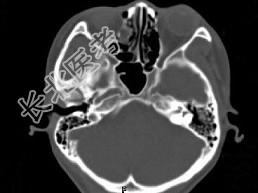

- 单项选择题女,25岁, 因眼部外伤来院就诊,CT如图所示, 最可能的诊断是 ( )

A、右侧颧弓骨折伴筛窦积血

B、右眼眶内侧壁骨折伴筛窦积血

C、右眼眶外侧壁骨折伴筛窦积血

D、右眼眶内外侧壁骨折伴筛窦积血

E、蝶骨骨折伴筛窦积血